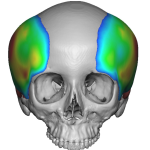

Female Custom Fronto-Temporal Head Widening Implants Case Example

Custom Fronto-Temporal Implants are patient-specific cranial implants designed to widen the upper temporal region and the lateral forehead in one continuous contour. They address the transition zone between the forehead and the side of the head — an area that strongly influences facial width and upper facial balance. What Area They Augment Fronto-temporal implants cover: Read More…